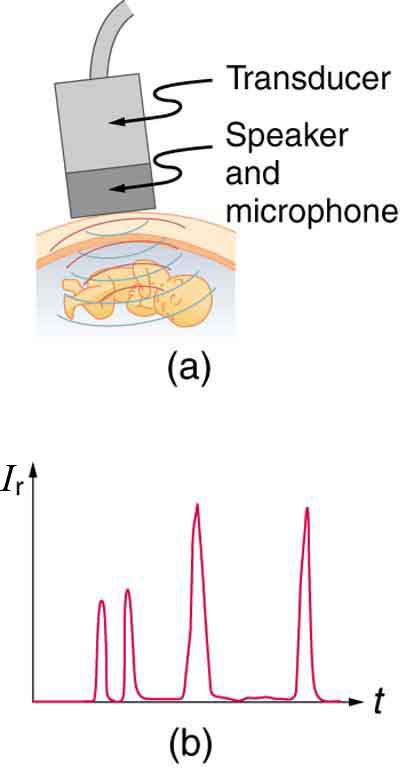

When used for imaging, ultrasonic waves are emitted from a transducer; that is a crystal exhibiting the piezoelectric effect—the expansion and contraction of a substance when a voltage is applied across it, causing a vibration of the crystal. These high-frequency vibrations are transmitted into any tissue in contact with the transducer. Similarly, if pressure is applied to the crystal in the form of a wave reflected off tissue layers, a voltage is produced that can be recorded. The crystal therefore acts as both a transmitter and a receiver of sound. Ultrasound is also partially absorbed by tissue on its path, both on its journey away from the transducer and on its return journey. From the time between when the original signal is sent and when the reflections from various boundaries between media are received, as well as a measure of the intensity loss of the signal, the nature and position of each boundary between tissues and organs may be deduced.

where and are the acoustic impedances of the two media making up the boundary. A reflection coefficient of zero (corresponding to total transmission and no reflection) occurs when the acoustic impedances of the two media are the same. An impedance match (no reflection) provides an efficient coupling of sound energy from one medium to another. The image formed in an ultrasound is made by tracking reflections (as shown in Figure 17.46) and mapping the intensity of the reflected sound waves in a two-dimensional plane.

The most common ultrasound applications produce an image like that shown in Figure 17.47. The speaker-microphone broadcasts a directional beam, sweeping the beam across the area of interest. This is accomplished by having multiple ultrasound sources in the probe’s head, which are phased to interfere constructively in a given, adjustable direction. Echoes are measured as a function of position as well as depth. A computer constructs an image that reveals the shape and density of internal structures.